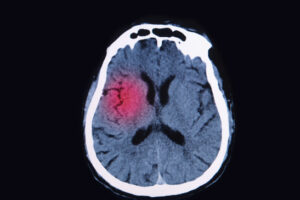

How much is a brain injury case worth in the State of Iowa?

Placing a value on case that involves a brain injury isn’t something that can be done in a matter of minutes. The truth is, these types of cases take time to assess and many factors need to be considered. For example, the severity of a brain injury is one factor that will play a large … Continue reading How much is a brain injury case worth in the State of Iowa?